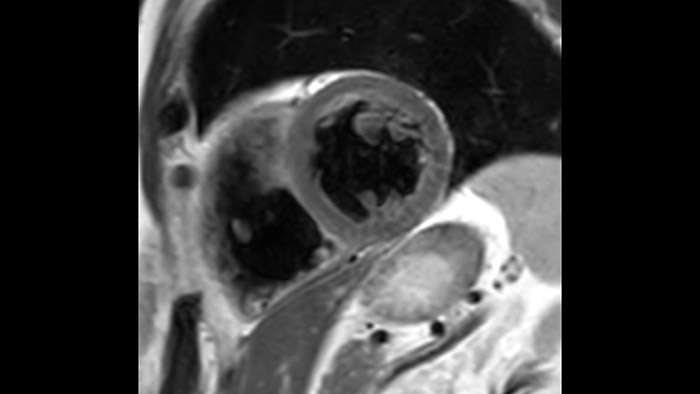

Diagnostic and prognostic utility of cardiac MR is increasing. Assess the anatomy and function of the heart using cine acquisitions, acquire information about perfusion and viability of the cardiac tissue, visualise potential edema with black blood sequence, access and even quantify tissue characterisation with CardiacQuant.

IntelliSpace Portal MR Caas5,6 Strain7 assists in patient diagnosis and monitoring by providing global strain parameters such as global longitudinal strain (GLS), global circumferential strain (GCS), and global radial strain (GRS), using short and long axis MR images, as well as describing the myocardium deformation- such as shortening, thickening, and lengthening during the cardiac cycle.